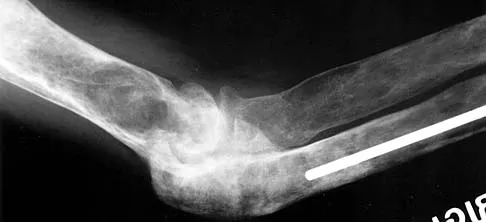

Figure 3 shows the radiographs of a 32-year-old man who fell 12 feet onto his outstretched arm and sustained a fracture-dislocation of the elbow. Initial management consisted of closed reduction of the dislocation. Surgical treatment should now include repair or reduction and fixation of the

The radiographs show fractures of the coronoid and radial head. The medial collateral ligament has been avulsed from the ulnar insertion, and there is a valgus opening on the medial side. The lateral collateral ligament is always disrupted in elbow dislocations and fracture-dislocations that occur secondary to falls. This is known as the terrible triad injury (dislocation and fractures of the coronoid and radial head); it has a very poor prognosis because of its propensity for recurrent or persistent instability and late arthritis. The principle in treating this injury is to repair all of the injured parts or protect them with a hinged external fixator until they heal. Norris TR (ed): Orthopaedic Knowledge Update: Shoulder and Elbow. Rosemont, IL, American Academy of Orthopaedic Surgeons, 1997, pp 345-354. Kasser JR (ed): Orthopaedic Knowledge Update 5. Rosemont, IL, American Academy of Orthopaedic Surgeons, 1996, pp 283-294.